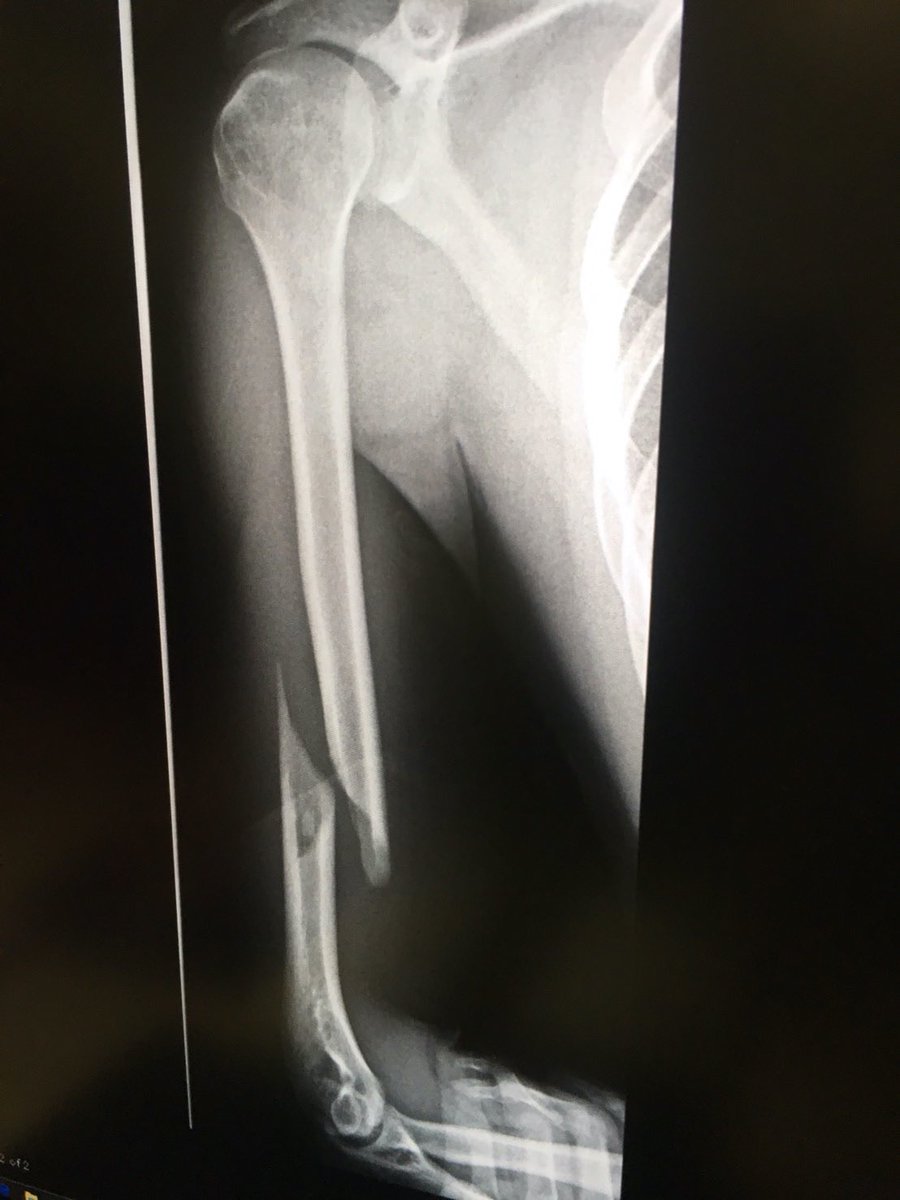

太ももの骨折った日に撮ったレントゲンをズボンにした

こんなエグい折れ方すんのか、痛そう

えぐいおれかた

粉砕や開放してないからマシなのか

大腿骨骨折ってたしかヤバいよね

何入れたんだろう。ロングネイル…γ?T2かな?とか考えちゃうのは職業病ですね…笑

綺麗に折れてる🦴

あぁ~痛そう💦

でもこれ治しやすい折れ方…

骨の質も良さそう…

この大腿骨骨折痛かっただろうな…考えたくもないな…